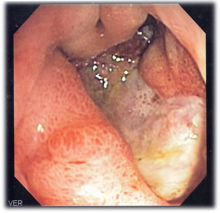

DIAGNÓSTICO

En los pacientes que presentan hemorragia

gastrointetsinal aguda alta, se recomienda la endoscopia temprana (en el

transcurso de 24 hrs.), para determinar con precisión el lugar de la misma. En

pacientes con gastritis corrosiva , la endoscopia permite determinar con

exactitud la extensión de la lesión.

Gastritis

atrófica

Puede ser el paso final de una gastritis crónica

que puede causar:

- desaparición de los pliegues (se observan los vasos sanguíneos de la submucosa);

- la pared de la mucosa se ha perdido en partes o en su totalidad.

Los factores desencadenantes son múltiples. Al

examen microscópico por lo general hay escasas glándulas (o ninguna); puede

haber cambios de metaplasia intestinal. Los síntomas clínicos son

inespecíficos, el diagnóstico se realiza por medio de la endoscopia y la

biopsia. Se ha discutido si la gastritis atrófica es precancerosa. En los

últimos estudios se ha encontrado un asociación con la anemia megaloblástica

pentilifome.

Gastritis

erosiva

Esta enfermedad se

puede tratar con un tratamiento que consiste en el reforzamiento de las paredes

del estómago a través de la boca.

La gastritis erosiva debería de estar descrita en el capítulo de úlceras. Mientras en aquella las erosiones son superficiales y múltiples, en la úlcera son más profundas y penetran a la capa muscular.